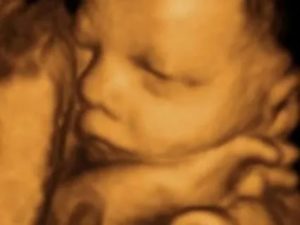

Водная оболочка (или плодный пузырь) — своеобразный «мешок», в котором разивается плод, со всех сторон омываемый околоплодными водами. В большинстве случаев количество жидкости к концу срока составляет примерно 800-1500мл. Воды постоянно обновляются, полный цикл обновления — около 3 дней.

Количество жидкости с течением беременности постоянно растет. В первом и втором триместре ребенок может еще сравнительно свободно перемещаться в матке, но уже к третьему триместру количество вод увеличивается, а с ними становится больше и сам ребенок, что приводит к сильной «тесноте».

На 33 неделе беременности у ребенка появляются черты лица: уши, ноги, брови руки, ногти, начинают расти волосы. Все системы, за исключением: дыхательной, иммунной и нервной, практически сформированы. Вес малыша на 33 неделе в среднем 2 кг, а рост достигает 43-44 см. На этом сроке возможно подтекание околоплодных вод, что может свидетельствовать о маловодии.